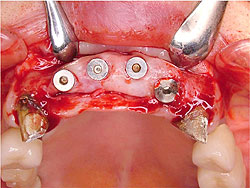

AQBは、結晶体の密度が高く純度も高いことが特長であり、三井記念病院におけるAQBインプラント症例では、最長18年を経過した臨床例においても、歯槽骨の状態は変わらず、逆に密になっていることが分かっている。そこで、上顎臼歯部の骨吸収症例において、サイナスリフトと同時にAQBインプラント1ピースを植立し、自家骨移植や人工骨移植を行わず、治療を行った症例を報告した。6例に施行し、全例、予後良好で、すべて植立後4ヵ月以内で咬合を開始した。GBR症例においてもAQBインプラント2ピースを埋入し、自家骨移植や人工骨移植は行わず、チタン入り非吸収性膜を用いたスペースメーキングを行った。その結果、4ヵ月後には歯槽骨の再生を確認した。

| AQBを用いて歯槽骨再生を図った症例 | |

GBR症例 ▼ ![]() 術前 ![]() 術直後 ![]() 膜除去直後 |